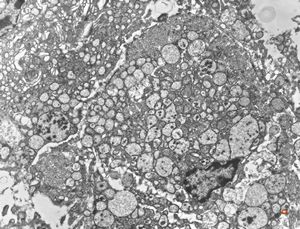

normal seromucinous salivary gland